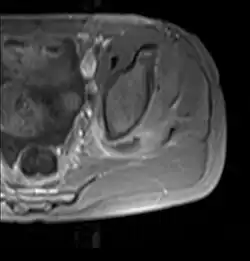

CT exam showing a multiloculated fluid collection in the left gluteus minimus muscle found to be a staph aureus pyomyositis in a 12-year-old healthy boy.

Coronal T2 weighted fat suppressed image showing a multiloculated fluid collection in the left gluteal musculature due to tropical pyomositis in a 12-year-old boy.